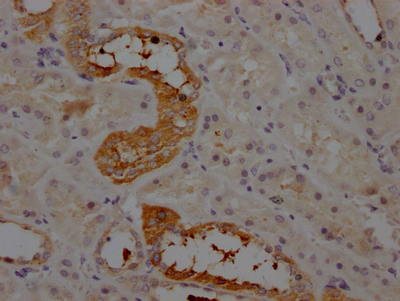

IHC image of CSB-RA263831A0HU diluted at 1:100 and staining in paraffin-embedded human kidney tissue performed on a Leica BondTM system. After dewaxing and hydration, antigen retrieval was mediated by high pressure in a citrate buffer (pH 6.0). Section was blocked with 10% normal goat serum 30min at RT. Then primary antibody (1% BSA) was incubated at 4℃ overnight. The primary is detected by a Goat anti-rabbit IgG polymer labeled by HRP and visualized using 0.05% DAB.